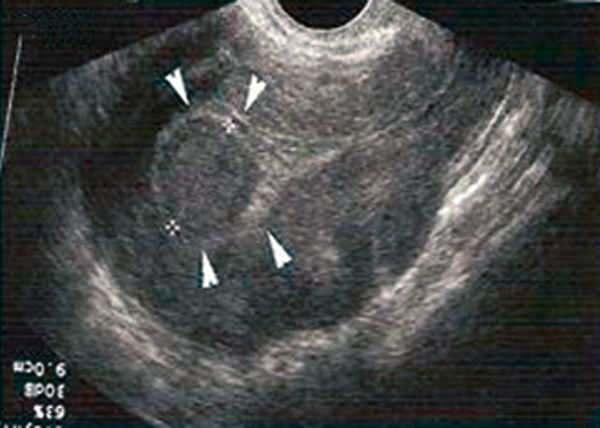

Quel est votre diagnostic ?

Il s'agit d'un fibrome utérin sous-muqueux. L'examen gynécologique par le toucher vaginal et le palper abdominal recherche une augmentation du volume de l'utérus dont les contours sont déformés par le ou les fibromes et/ou une masse latéro-utérine mobile avec l'utérus. L'échographie confirme le diagnostic en visualisant une masse bien limitée iso- ou hypo-échogène sans renforcement distal et développée aux dépens de l'utérus.